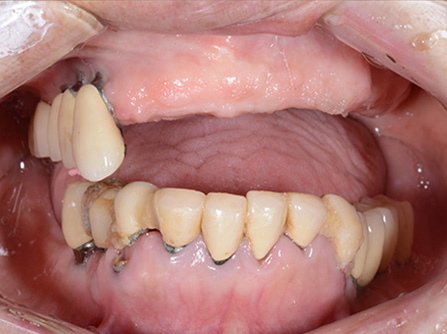

症例2

歯がグラグラで噛めない。骨が少なくてインプラントできない。という主訴でご来院頂いた患者様に対して「特殊プラスティック義歯」を使用した入れ歯の症例

術前

入れ歯での治療後